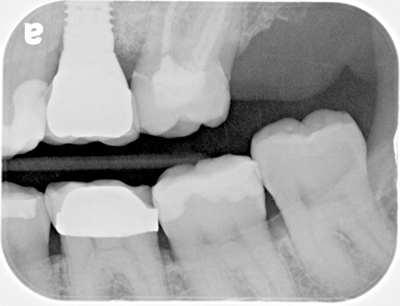

A 55-year-old female presented to my office for an evaluation of a crown placed on tooth No. 15 within the last few years. Her complaints included: "It feels big. I get a ton of food trapped in it, and it is kind of ugly." A bitewing was taken (Fig. 1) revealing an ill-fitting crown on No. 15. An intraoral photo was also taken (Fig. 2) confirming an oversized PFM with poor contours. The decision was made to remove and replace the crown.

FIG. 2